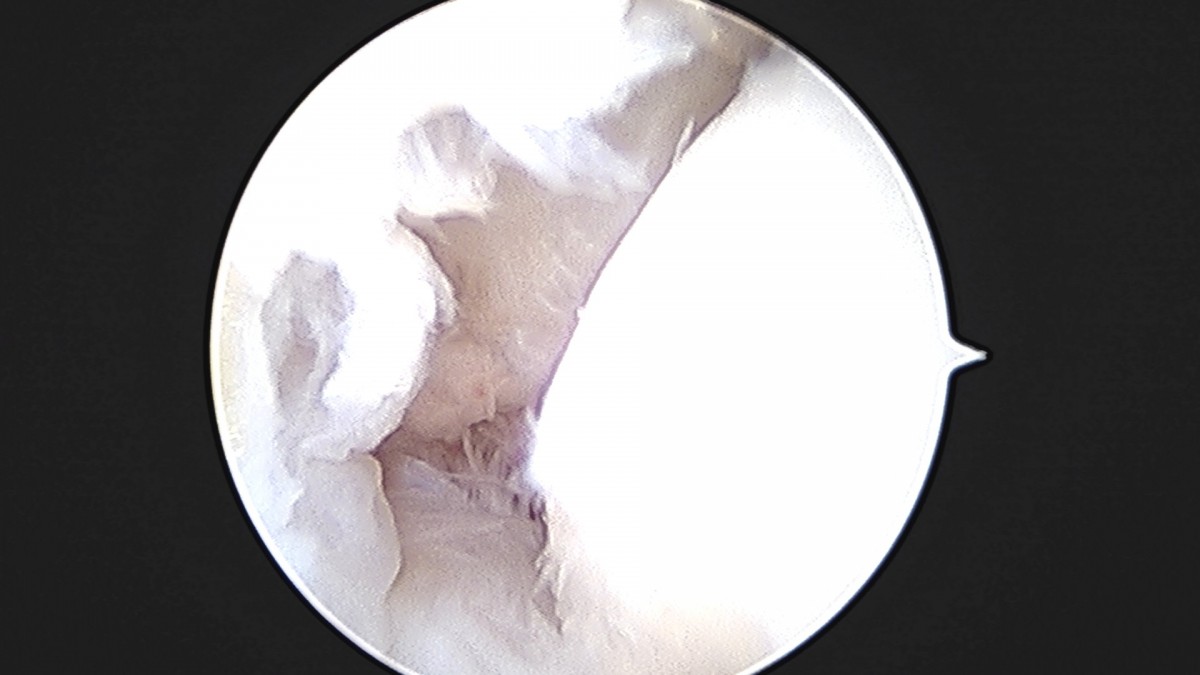

이재상원장님 발목 인대 봉합술 이지O 환자

작성자 최고관리자 댓글 0건 조회 681회 작성일 25-09-16 16:26